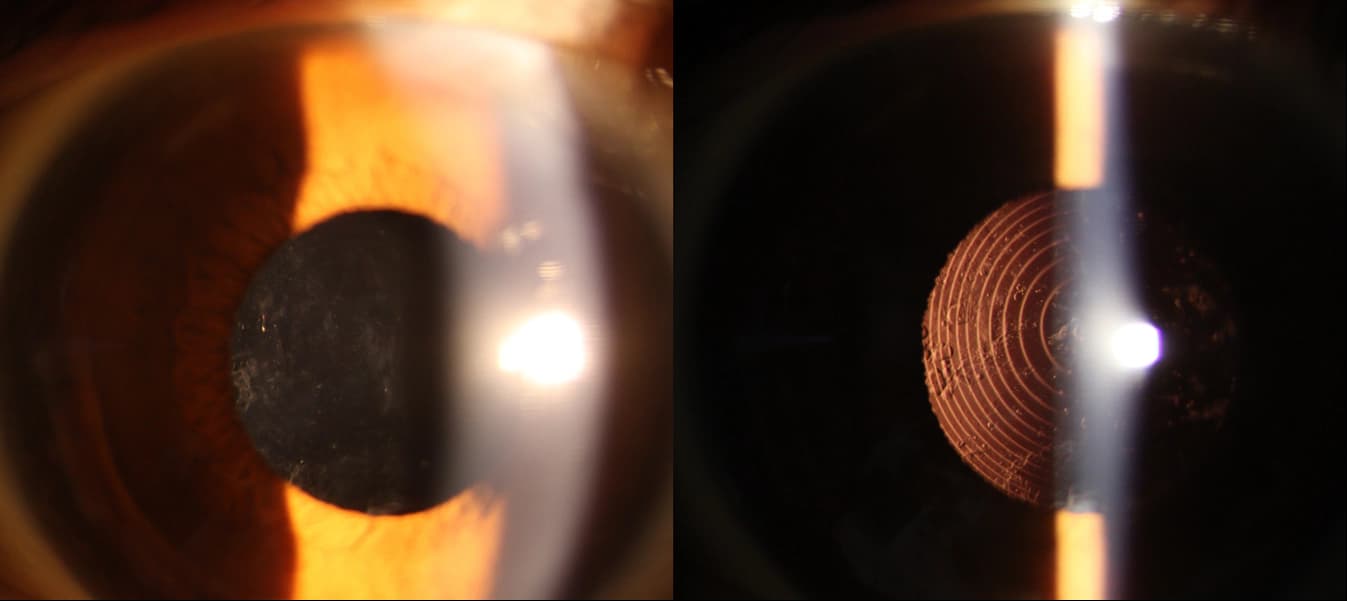

후발성 백내장 치료 전

후발성 백내장 치료 후